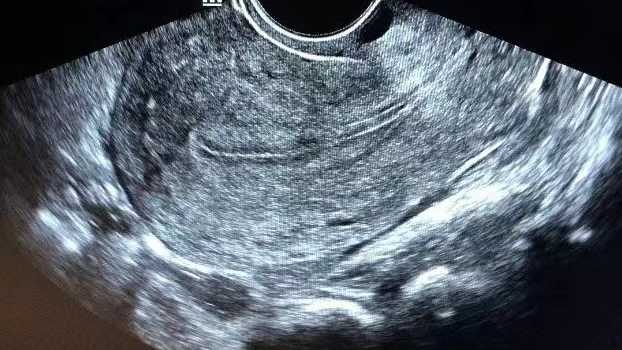

在针对子宫内膜的B超检查中,我们通常会将内膜情况分为A、B、C 三种类型,那到底哪种类型的内膜移植成功率更高?一起来看看吧~

常见于月经第6-10天(月经基本结束),内膜厚度约为4-9mm,超声下能看见清晰的三条线,构成“三线征”(宫腔线、前后壁内膜线清晰)。